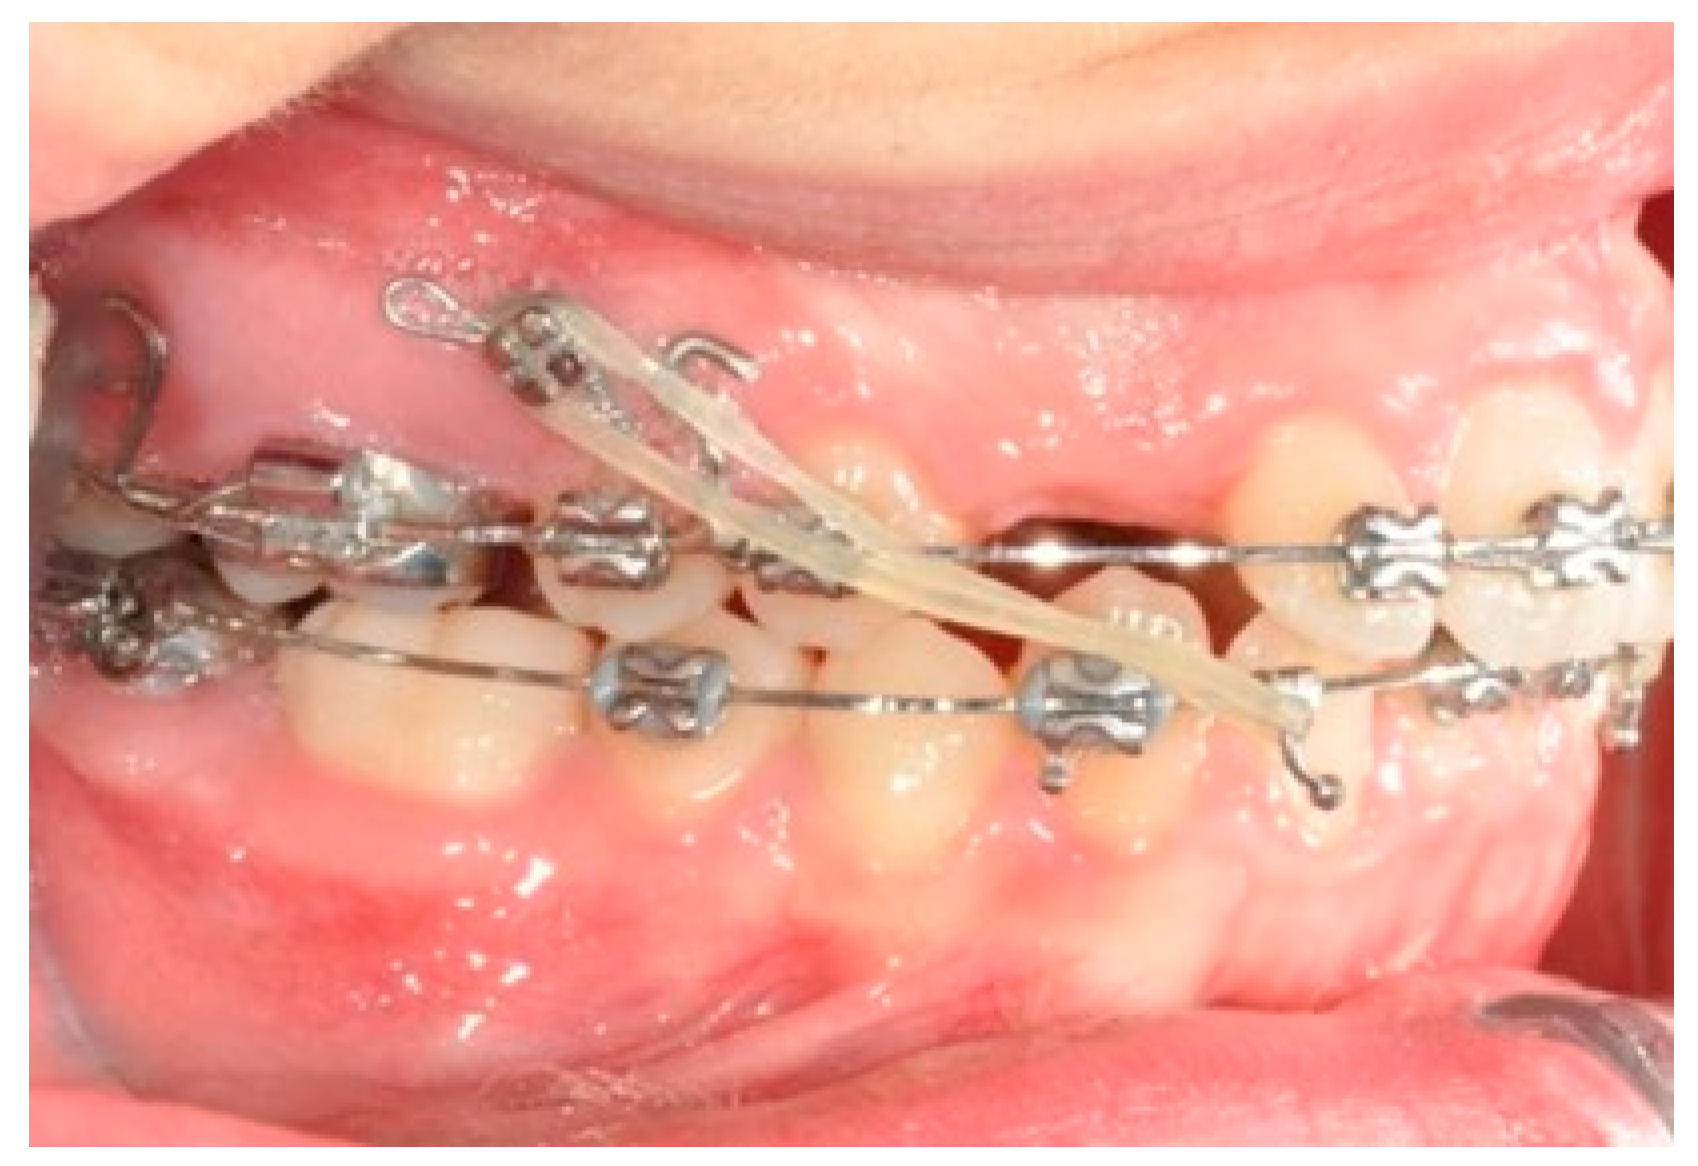

Figure 6. Molar and premolar distalization strategy: Hooks are placed between the laterals and the cuspids. Third-class elastics (1/4” 6 0z) are placed from the tads to the hooks.

After tad positioning, sequential bonding is applied on the lower arch. An 18 × 0.25 SS arch is shaped, adding a maximum 10° distal tip to the second molar. Hooks are placed between the laterals and cuspids. Third-class elastics (1/4” 6 0z) are placed from the tads to the hooks (Figure 6). The distal tip on the lower second molars will produce a gain of space between molars, with the space needed for the management of the spee curve and the recovery of IMPA.